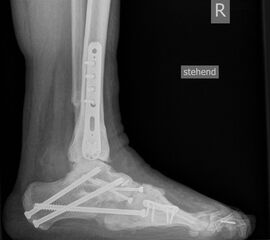

• Fuß belastet dp und seitlich (Abb. 14 und 15)

• Saltzman view (Abb. 16)

Zum Lesen der Bildbeschreibung und zur Vollansicht bitte die Bilder anklicken. Bilder: A. Simon

Typische Merkmale der Standard-dp-Röntgenaufnahme des Fußes im Stand

• Talus und Calcaneus verlaufen fast parallel

• Os naviculare ist gegenüber dem Talus nach medial gedrängt

• Metatarsalia überlappen sich basisnah

• Metatarsale I erscheint verkürzt

• Metatarsus adductus

Typische Merkmale der Standard-Seitaufnahme des Fußes im Stand

• Knöchelgabel ist außen rotiert

• Sinus tarsi ist einsehbar

• Subtalare Gelenklinie verläuft horizontal und ist breit einsehbar

• Der Abstand Malleolus medialis zum Os naviculare ist verkürzt

• Der Calcaneus erscheint verkürzt

• Der Krümmungsscheitel des Fußes ist erhöht

• Calcaneus pitch ist meist erhöht, der Rückfuß Equinus ist eher selten 12

Typische Merkmale des Saltzman View

• Calcaneus steht varisch zur Tibialängsachse

• Der erste Zehenstrahl ist medial erkennbar

• Konsekutive varische Gelenklinie des oberen Sprunggelenkes